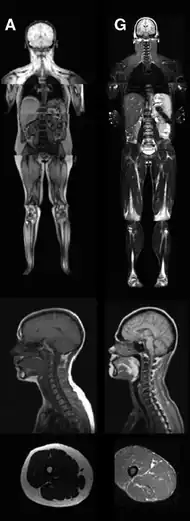

An MRI image illustrating the lack of subcutaneous fat of a patient with the disease (G) compared to a control patient (A) | |